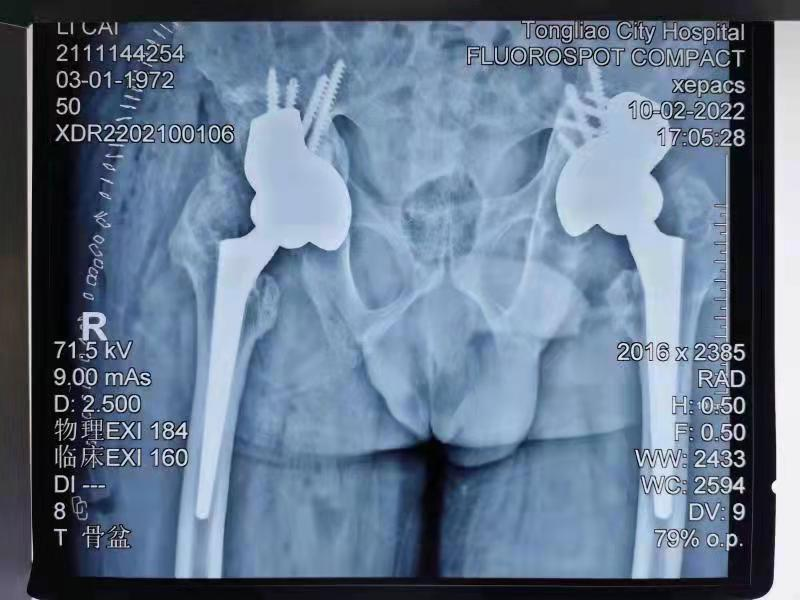

董谢平教授与燕飞主任共同主刀该项手术,在西院手术室全麻下分两次完成了这种高难度手术,术后效果满意。现患者已出院康复中,术后X线显示双侧假体位置良好。